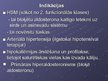

Diurētiskie līdzekļi

Diurētiskie līdzekļi

Diurētiskie līdzekļi